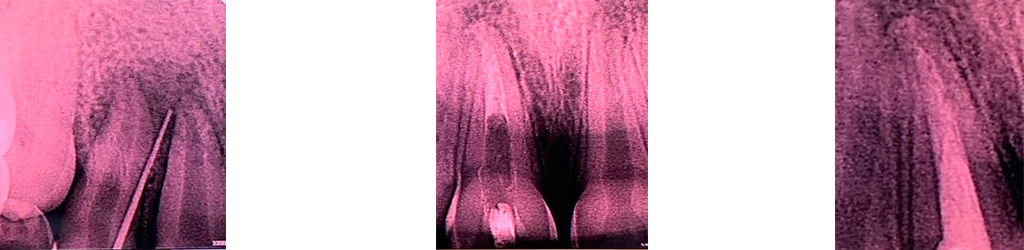

Root canal infections also called periapical (PA) lesions are characterized histologically by fibrous and granulation tissue infiltrated to varying degrees by acute and chronic inflammatory cell. The main purpose of this clinical study was to assess the treatment of periapical lesion and infection and results up to 6 months after endodontic treatment of teeth with periapical pathology using a new MTA sealer.

A 10 year old girl reported to the clinic with the complaint of swelling and pain of anterior right upper region. The IOPA x-ray evaluation revealed periaical lesion. Treatment started with root canal treatment of the affected tooth. After access preparation using endo z bur, repeated canal irrigation was done using sodium hypochlorite 3%. After completing biomechanical preparation with protaper gold repeated dressings were done using metapex and tri antibiotic paste. After waiting for few months the root canal filling was done using latest filling material MTA, MTA, present in the composition of MTA Fillapex, is more stable than calcium hydroxide, providing constant release of calcium ions for the tissues and maintaining a pH which elicits antibacterial effects. The tissue recovery and the lack of inflammatory response are optimized by the use of MTA. Thus, MTA Fillapex is considered a great material for root canal treatment, considering its bioactive potential.

THIS BIOACTIVE MATERIAL HELPED US ACHIEVE GREAT RESULTS IN TERMS OF HEALING AND FUNCTIONALITY.